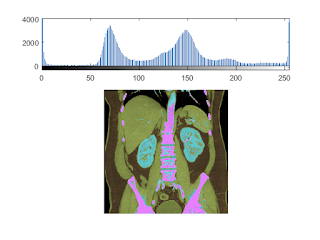

filtering demo on the CT data

clf;

imagesc(I);colormap(gray);

title('unfiltered');